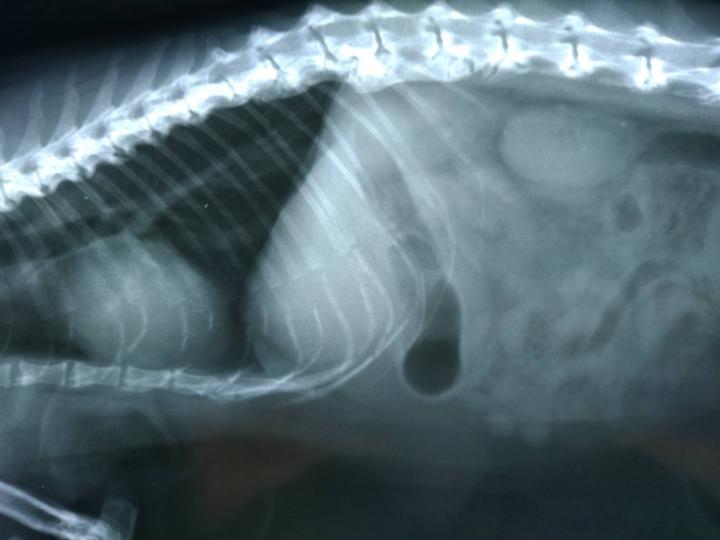

あれ?でも、お母さん。何で背骨のレントゲンばかりなの?骨軟骨異形成症候群だったら、足か尾だけだよね?

え?先生が「背骨にカルシウムが蓄積してる」って

あ、それは骨軟骨異形成じゃなくて、変形性脊髄症じゃないかな?

調べてみたらですね、変形性脊髄症は、何らかの原因で、体が背骨を補強しようとして、カルシウムが集まり、それが突起などの変形をして場合によっては痛みから歩行困難等になるらしいです。

直接、先生から聞いていないので解らないのですが、骨折の後もあったとか。